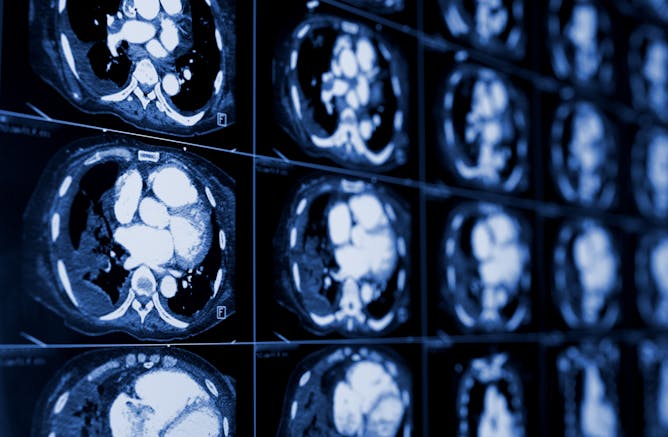

In my previous life as a clinical researcher, my co-workers and I would joke it was fitting that the lung cancer awareness ribbon is colored an inconspicuous pearl white. Compared with the ubiquitous marketing around breast cancer or the growing attention on colon cancer, lung cancer advocacy can seem practically invisible.

Yet, more people around the world die of lung cancer than all other cancers – in part because many people who are eligible for lung cancer screening don’t actually get screened, including most Americans.

Dr. Nina Thomas, a pulmonologist at the University of Colorado Anschutz Medical Campus, writes that difficulty accessing and paying for lung cancer screening plays a big role in low screening rates. Stigma and fear are additional deterrents. But lung cancer is neither a death sentence nor a moral failing.

“When diagnosed early, doctors treat lung cancer with an intention to cure,” Thomas writes. “Reassurance and education around next steps and paths to treatment at the time of screening help diffuse some of the distress surrounding lung cancer.”

Lung cancer screening can save lives, but it isn’t accessible to everyone at risk of developing the disease.

Stigma, fear and cost prevent many patients from getting screened for lung cancer. This can prove deadly for the most vulnerable.